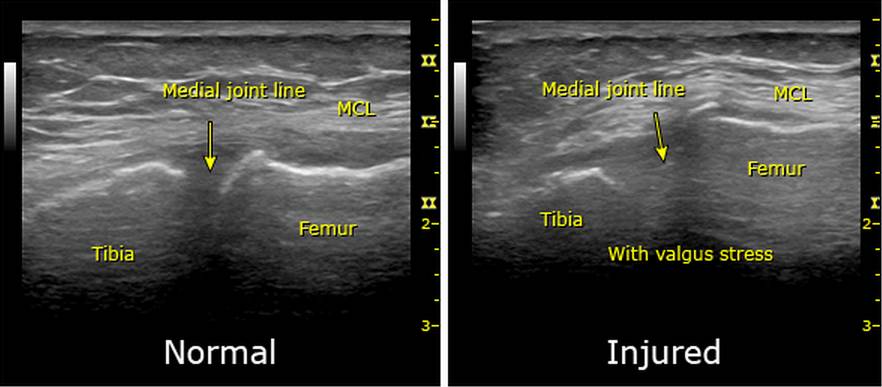

一些观察性研究及个案报道认为床旁超声可很好地评估内侧副韧带撕裂,他们根据超声的异常表现及关节间隙打开程度的量化评估确定内侧副韧带的病变区域(图9)。不过关于超声对于内侧副韧带损伤的诊断意义仍需要大量的高证据等级的研究进行论证。

图9,内侧副韧带损伤时的超声影像,内侧副韧带损伤使得膝关节内侧间隙增大。